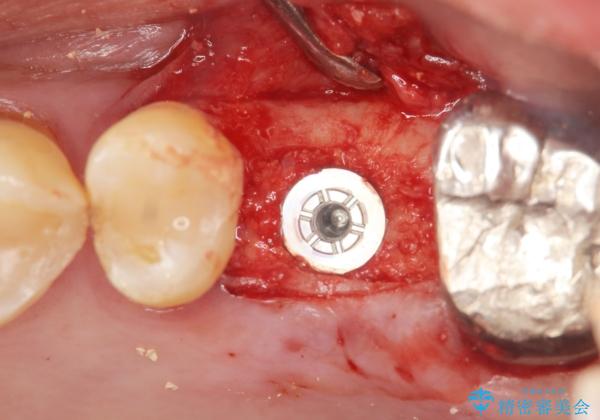

精査したところ上顎骨の厚みが薄かったため、ソケットリフト(上顎洞底挙上術)を併用してインプラント治療を行いました。

インプラントの種類:スプライン ツイスト (保証期間:5年)

- 外科手術のため、術後に痛みや腫れ、違和感を伴います